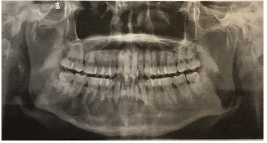

以下图为例:

上图曲面体层片显示下颌骨多囊性、透射性改变,边界清楚;病变沿颌骨长轴扩展,颌骨无膨隆;右下颌前牙牙根吸收呈斜面状。